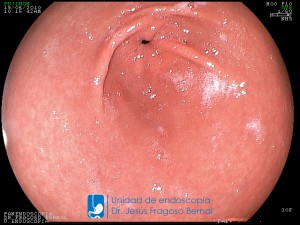

La Unidad de Endoscopía fue creada en 2002 por el Dr. Jesús Fragoso Bernal, es pionera en el estado por la utilización de la tecnología más avanzada, que nos permite ofrecer servicios integrales de diagnóstico y tratamiento para las enfermedades del aparato digestivo.